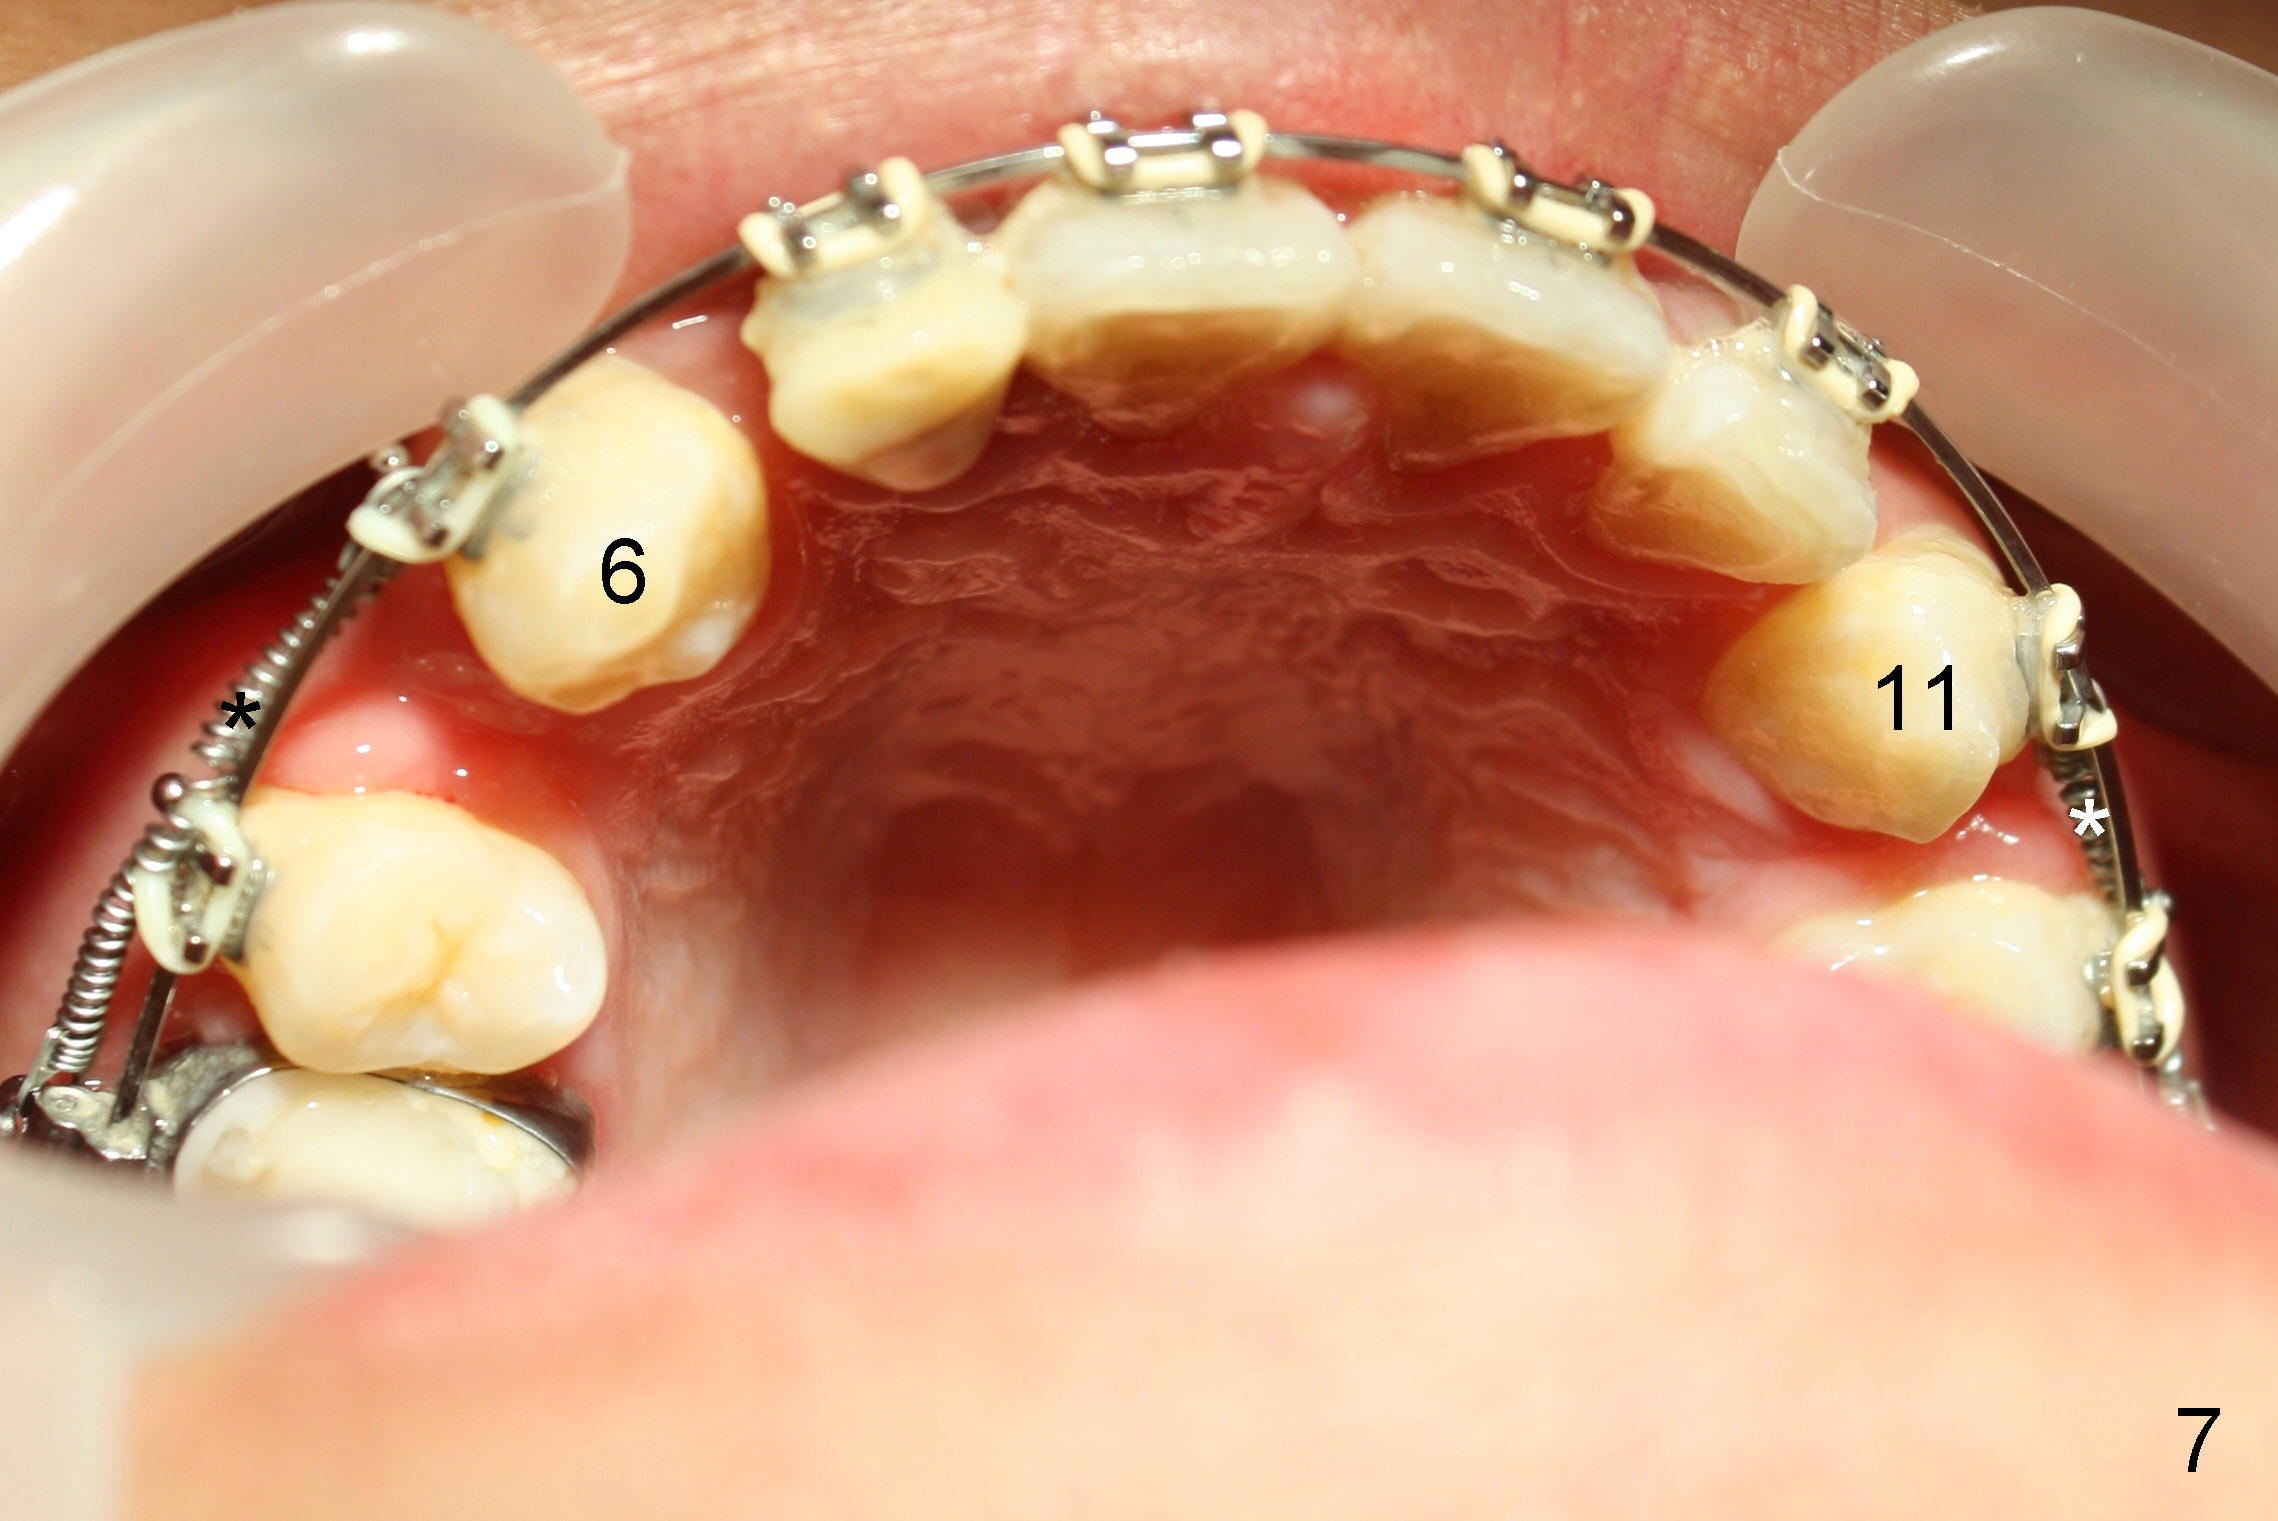

The 1st step of ortho is arch wire sequence to align the arches (from thin round wires to thick rectangular ones). The 2nd is to retract the canines distal (Fig.1 (planning), Fig.7 (6 months post bracketing), Fig.8 (7 months), using closed coil springs (*). The 3rd step is to move the remaining anteriors together distal using posted wire (^) and again closed coil springs (Fig.9; 8 month into treatment). Note the overjet between upper and lower anteriors (Fig.9: *). This space allows the upper incisors to move backward.

The patient returns 1 month post distalization of the upper incisors (Fig.10-12, 9 months of treatment). Bilateral canine relationship is Class I (Fig.11,12). All needs to be done is to continue distalizing the upper incisors or slightly mesialize the canines if indicated.